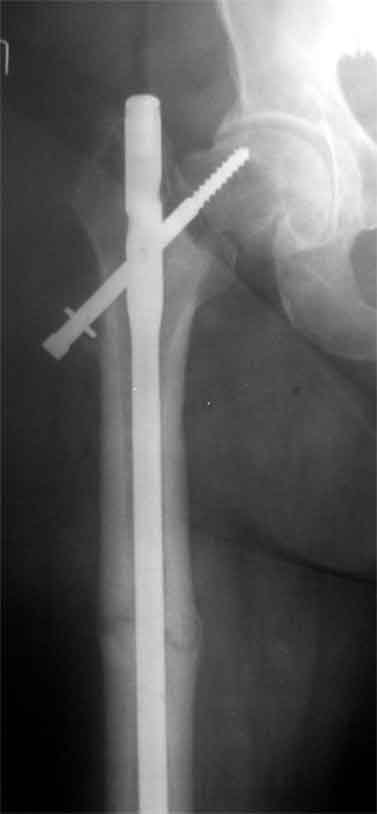

Доброго время суток, коллеги. Обратилась на консультацию пациентка 52 лет. травма и первичный остеосинтез перелома бедра около года назад, далее был обнаружен перелом шейки бедра (возможно ятрогенный), реостеосинтез реконструкционным гвоздем 8 месяцев назад. Конченость не опорна. В больнице, где выполнялись эти вмешательства предложили выполнить THR с длинной ножкой. Возможно ли в такой ситуации добиться сращения шейки при помощи каких-либо остеотомий?

На мой взгляд дистальный перелом срощен, а состояние тазобедренного сустава и молодой возраст пациентки позволяют произвести вальгизирующую остеотомию проксимального бедра. В случае, если нет сращения дистального перелома можно фиксировать длинным DHS; Если есть сращение- обычным DHS.

Коллкега на представленных снимках имеется ротационная стабильность и плохо репонированный перелом. В данный момент думать об эндопротезтровании или межвертельной остеотомий рано, так как перелом диафиза бера еще полностью не сросся, я думаю, надо на данном этапе попытаться стабилизировать перелом шейки бедра конюлированными винтами, удалить проксимальный винт, попытатся сделать репозицию, хотя маловероятно, что получется добиться улучшения, и стабилизировать 3 конюлированными винтами и дать компресию, таким образом дать шанс, может перелом срастется до удаления штифта. Удачи

Применение одного импланта для лечения ипсилатеральных переломов резко ограничено из-за риска осложнениий, связанных с применением неадекватной фиксации. По литературным данным, осложнения после применения зарекламированных реконструктивных гвоздей для лечения ипсилатеральных переломов доходили до 56%.

Несостоятельность фиксации шейки не давала возможности срастись перелому, потому что запланированнная динамическая нагрузка в большинстве случаев прекращалалась из-за вторичного варусного смещения шейки.

В данном случае навряд ли можно ожидать образования сращения на бедре и еще имеется укорочение засчет варуса.

поможет установит сращение на шейке и бедре. Восстановление длины можно сделать за счет вальгусной остеотомии оригинальным методом Blade Plate. На бедро шт ифт ретроградно или пластина, кому что нравится. На мой взгляд, еще имеется шанс спасти головку остеотомией.